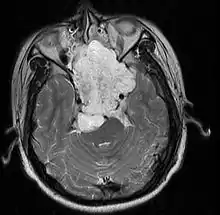

Skull Base

- Hannover; 2007 (Germany) PMID 17695386 -- "Chordomas of the skull base: surgical management and outcome." (Samii A, J Neurosurg. 2007 Aug;107(2):319-24.)

- Retrospective. 49 patients. Transethmoidal approach 36%, pterional 23%, retrosigmoid 23%.

- Outcome: GTR 49%, subtotal resection 51%. Initial surgery GTR 78%. 5-year OS 65%, 10-year OS 39%

- Toxicity: New neurological deficit 12%

- Conclusion: Chordoma cannot be regarded as surgically curable tumors, given the 5- and 10-year OS